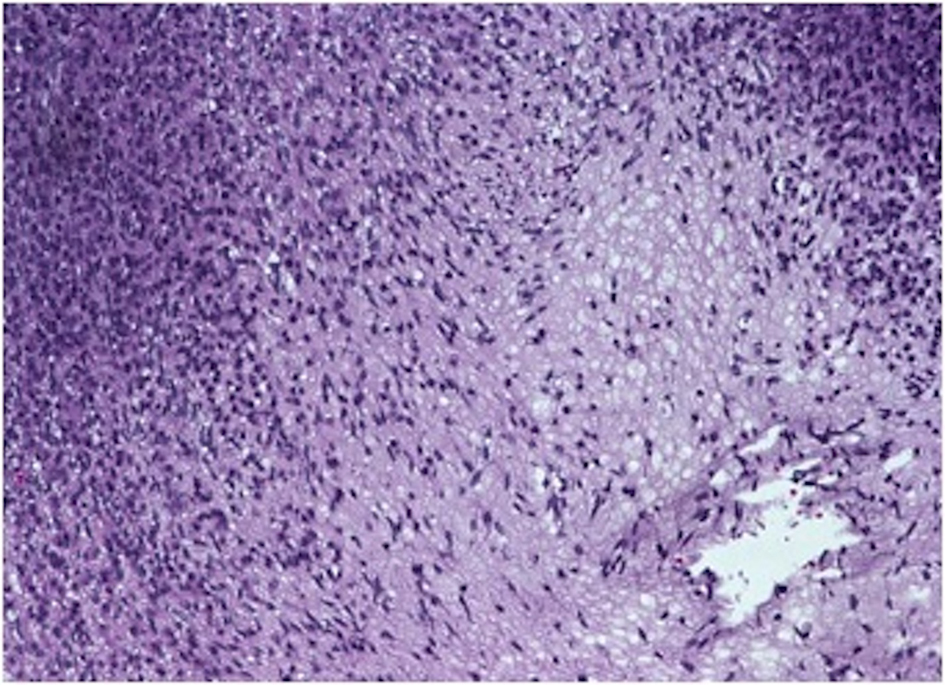

On gross examination, the biopsy specimen had a shiny appearance suggesting myxoidal features along with other areas of hemorrhage (Fig. 4). On histopathological examination (Fig. 5, 6), the specimen again revealed myxoidal features with small round blue cells and other areas of spindle cells arranged in a wavy streamline pattern. There were also areas of high mitotic activity. Histochemically, the specimen stained positive for vimentin and CD99. It stained diffusely positive for S100 and had patchy staining for NSE. It stained negatively for CD31, CD34, desmin, melan-A, SMA, pan-keratin, EMA, CD45, CD56, chromogranin, and synaptophysin.

![]() Click for large image | Figure 5. 20 × view with spindle cells and areas with loose and dense matrix of small round blue cells. |

![]() Click for large image | Figure 6. 40 × view with small round blue cells as well as spindle cells arranged in a wavy fasicular pattern suggestive of neural origin. |